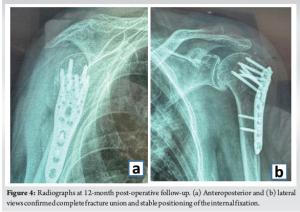

At the 12-month post-operative follow-up, the patient demonstrated excellent clinical outcomes. She reported no pain (15 points) and unrestricted performance in activities of daily living (20 points), including the ability to position her hand above her head. Range of motion assessment revealed active pain-free forward flexion of 110° (6 points)and abduction of 87°(4 points). Functional external rotation allowed her to comb her hair (7 points), and functional internal rotation reached the T7 spinous process level (10 points). Strength assessment indicated the ability to lift over 2 kg (21 points). The total Constant-Murley score was 83 points. Radiographic evaluation at 12 months (Anteroposterior and lateral views) (Fig. 4) confirmed complete fracture union and anatomical positioning of the internal fixation devices without migration. Furthermore, there were no signs of avascular necrosis of the humeral head or recurrent dislocation.